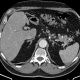

Здравствуйте, подскажите пациент 60 лет, особо жалоб нет, на узи было изменения в печени, в хвосте поджелудочной железы отмечаются немного гиподенсивные изменения может ли это быть раком? на МРТ лучше покажет?

В печени гиперваскулярное образование в 5 сугменте, требует наблюдения. Поджелудочная - ничего плохого не вижу. А вот лимфоаденопатия выражена. Если мтс, то откуда - не знаю